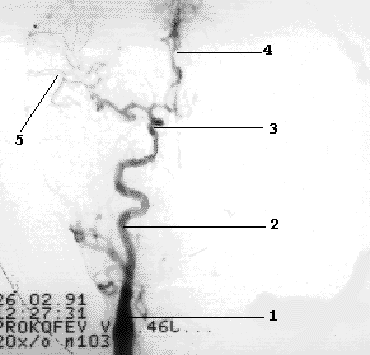

Наружная сонная артерия имеет короткий ствол, делясь на ряд ветвей, что легко позволяет отличить ее от ВСА. Насчитывают девять ветвей НСА, ряд из которых (терминальные ветви лицевой, поверхностной височной и верхнечелюстной артерий) анастомозируют с конечными ветвями глазничной артерии (первая интракраниальная ветвь ВСА) (Рис 1.4).

Рис 1.4.

Схема глазничного анастомоза. 1- ОСА, 2- НСА, 3- лицевая артерия, 4- ПВА, 5- ГА, 6-глазничный анастомоз.

Внутренняя сонная артерия до входа в полость черепа ветвей не дает. Непосредственно после выхода из кавернозного синуса она отдает первую ветвь глазничную артерию, а затем делится на две конечные ветви - переднюю мозговую артерию и среднюю мозговую артерию (Рис 1.5).

Рис 1.5 Интракраниальные ветви ВСА. 1- ОСА, 2- ВСА, 3- сифон ВСА, 4- ПМА, 5- СМА.